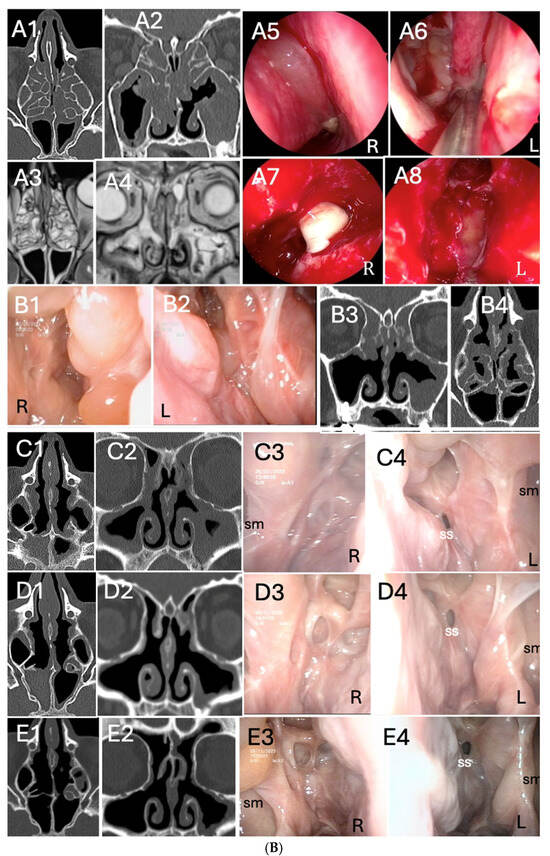

Three representative cases of radiologic and endoscopic outcomes before and after dupilumab treatment, according to basal Access Score and previous surgery, are reported in Figure 3A–C. Out of 32 patients, 2 underwent “adequate” Full House FESS of revision for relapsing CRSwNP during dupilumab treatment (one reported in Figure 3B).

Figure 3.

(A). Radiological and endoscopic (R = right, L = left) images in relation to dupilumab therapy without surgery in CRSwNP (eosinophils>30/hpf). (A1–A4): start of dupilumab. Axial (A1) and coronal (A2) computed tomography (CT) images show pansinusitis. Endoscopic examination (A3,A4) of both nasal cavities shows polypoid formation completely occupying the nasal fossa (total NPS = 7) S:sinus; TI:turbinate. (B1,B2): 6 months after initiation of dupilumab. Sphenoidal (B1), frontal and maxillary sinuses (B2) completely disease-free. Pictures (C1–C4): 12 months after initiation of dupilumab. Radiologic (C1,C2) and endoscopic examination (C3,C4) of both nasal cavities show significant reduction of polypoid mass. (D1,D2): axial (D1) and coronal (D2) computed tomography (CT) images 18 months after initiation of dupilumab. Outcomes are maintained in the long run. (E1–E4): 24 months after initiation of dupilumab. Maintenance of the radiological (E1,E2) and endoscopic (E3,E4) outcomes is evident, even at long term follow-up visit. (B). Radiological and endoscopic (R = right, L =left) images in relation to dupilumab therapy after “adequate” Full House FESS of revision for CRSwNP. (A1–A4): CT (A1,A2) and MRI (A3,A4) images showing CRSwNP recurrence after two “not adequate” FESS (ACCESS score 20/24). Intra-operatory images (RESS): (A5) right nasal fossa NPS = 4; (A6) debridement of nasal polyps; (A7) left maxillary sinus empyema; (A8) frontal sinusotomy. (B1–B4): start of dupilumab 18 months after “adequate” Full House FESS, following CRSwNP relapse (eosinophils>50/hpf). Endoscopic (B1,B2) and radiological (B3,B4) images, ACCESS score 2/24. (C): 6 months after initiation of dupilumab. Radiologic (C1,C2) and endoscopic examination (C3,C4) of both nasal cavities shows partial reduction of polypoid mass. (D1–D4): 12 months after initiation of dupilumab, a local control of the disease is evidenced in both axial (D1) and coronal (D2) computed tomography (CT) and endoscopic (D3,D4) images (E1–E4): 24 months after initiation of dupilumab, images highlight the maintenance of the radiological (E1,E2) and endoscopic (E3,E4) results even at long term follow-up visits. Inferior turbinates are preserved, while middle turbinate was remodeled for correct sinus ventilation and disease control. “ss”: sphenoid sinus; “sm”: maxillary sinus. (C). Radiological and endoscopic (R = right, L = left) images in relation to dupilumab therapy after “adequate” salvage Full House FESS in patient who underwent two previous “not adequate” surgeries (last surgery performed 18 months before starting dupilumab). (A1–A4): The patient started biologic treatment with dupilumab. Coronal (A1) and axial (A2) CT scans evidenced ethmoidal cells still not opened and hyperostosis of the anterior and posterior compartment. Endoscopic images (A3,A4): NP relapse and tissue remodeling. (B1–B4): 6 months after initiation of dupilumab, persistence of nasal polyps seen radiologically (B1,B2) and endoscopically (B3,B4). (C1–C4): 18 months after initiation of dupilumab, ACCESS score 22/24 (C1,C2). Endoscopic sinus surgery (C3,C4) was performed in this patient, keeping on treatment with dupilumab. (D1–D4): 1 year after “adequate” Full House FESS and 3 years after dupilumab. TC scans (D1,D2) evidenced paranasal sinuses fully opened. Corresponding endoscopic image (D3,D4).